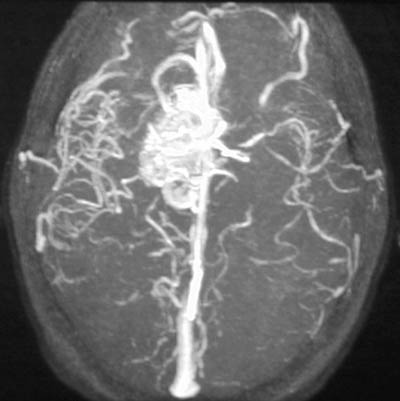

| In the angiogram above there is a vascular malformation in the right medial frontal lobe. There is contrast in the arterial branches of the left internal carotid, while there is continued venous drainage from the vascular malformation on the right. This vascular malformation was supplied by a pericallosal branch of the anterior cerebral artery. This patient had a history of severe headaches for years. Some patients may have seizures. In the axial MRA image below, the vascular malformation can be seen to drain into the superior sagittal sinus. |